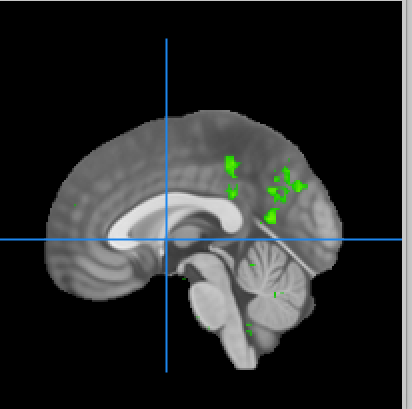

Neurosynth term: “episodic memory”

Neurosynth map for the term

Brain region chosen for the term

Other Neurosynth terms associated with this brain region